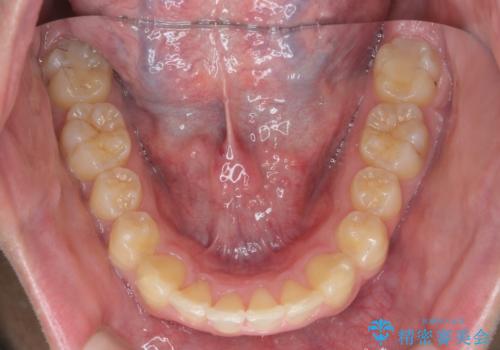

ガタつきの大きい前歯 インビザラインによるマウスピース矯正治療

食事・歯ブラシ時以外の時間にしっかりとマウスピースを装着していただけたのでガタつきは大きく改善し良好な歯並びを得ることができました。